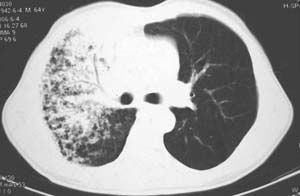

右肺上叶见片状 网格状及索条致密影.其内参杂斑点状小结节,部分融合,密度不均匀,内见含气支气管像,纵隔内见肿大淋巴结,其他肺呈代偿性肺气肿像.结合男 64  咳血,咳痰 发热 3天 血象1.2万,综合考虑:1 慢性炎症伴间质纤维化 肺气肿.2 不除外特发性感染的可能.

右肺上叶大片片状、网格状及索条致密影,前半部密实向后逐渐疏松,其内参杂斑点状小结节,密度不均匀,内见含气支气管像,纵隔内见肿大淋巴结,其他肺呈弥漫性小叶中心性性肺气肿改变,结合男 64  咳血,咳痰,发热3天,血象1.2万。考虑:1 慢性支气管炎、肺气肿合并右上肺感染。2 不除外结核合并感染的可能。

右肺上叶见片状 网格状及索条致密影.其内参杂斑点状小结节,部分融合,密度不均匀,内见含气支气管像,前段有一小片结影,纵隔内见肿大淋巴结,右侧胸腔少量积液。.结合男 64  咳血,咳痰 发热 3天 血象1.2万,综合考虑:2 右上肺感染伴间质纤维化 2 警惕细支气管肺泡癌。3建议结合临床及进一步检查[痰及纤支镜]或治疗后复查

右侧胸廓略小于左侧,右肺上叶大片实变影,近肺门处密度较高,内见支气管气相,周围较淡,呈网格状,余肺野清晰,纵隔内见肿大淋巴结,右侧胸腔少量积液。临床 咳血,咳痰 发热 , 血象1.2万。

考虑大叶性肺炎。

右侧胸阔塌陷,纵隔右移。右上肺大片状高密度影,沿支气管血管束走行,内见点状钙化;支气管充气征阳性,支气管呈柱状扩张;胸膜下小叶间隔增厚;右侧后胸壁内侧见带状水样密度影;纵隔淋巴结增大。

考虑:①右上叶陈旧性结核合并感染可能大。②右侧少量胸水。

影像学表现:右肺上叶大片状、网格状及索条致密影,前半部密实向后逐渐疏松,其内参杂斑点状小结节,密度不均匀,内见含气支气管像,纵隔内见肿大淋巴结.

综上,以右上肺tb(干酪性肺炎)首先考虑.当然大叶性肺炎不能除外.(血象不是特别高,纵隔内淋巴结肿大,也不甚支持.).如果经积极抗感染治疗,病灶明显好转.更能明确为大叶性肺炎.也不能明确排除肺ca.建议痰培养和纤支镜.

右肺上叶见片状,网格状及索条样致密影,内见支气管气相,纵隔内见肿大淋巴结,同侧胸腔内少量液性密度影,余肺呈肺气肿改变,临床:男,64岁,咳血,咳痰,发热3天,wbc---1.2万

考虑:1)右肺大叶性肺炎2)肺气肿